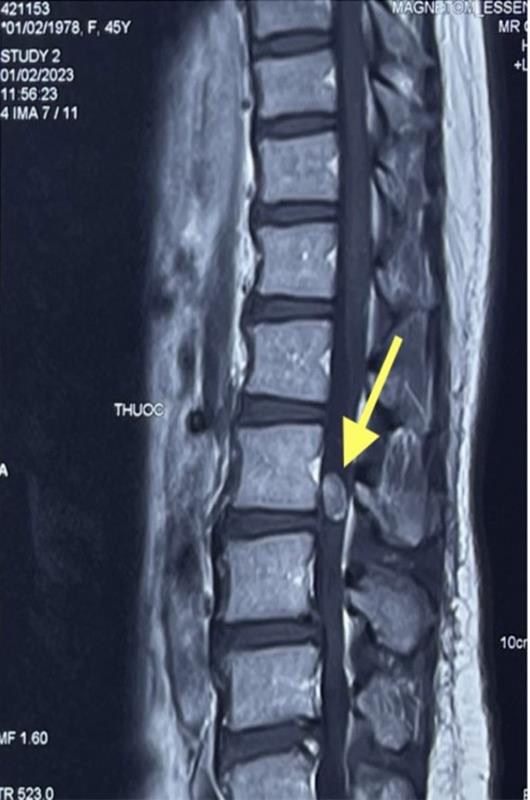

Kết quả chụp MRI cột sống thắt lưng, bác sĩ Bệnh viện Quốc tế Hoàn Mỹ Đồng Nai phát hiện bệnh nhân có 1 khối u trong ống sống, chèn ép rễ thần kinh chùm đuôi ngựa. Đây là nơi tập hợp các dây thần kinh ở phần cuối của tủy sống, chi phối vận động, cảm giác cho 2 chân và chức năng kiểm soát tiểu tiện của cơ thể. Nếu không can thiệp lấy khối u, người bệnh sẽ dần bị mất kiểm soát tiểu tiện và yếu liệt dần 2 chân.

Vị trí khối u trong ống sống hiển thị trên phim chụp MRI